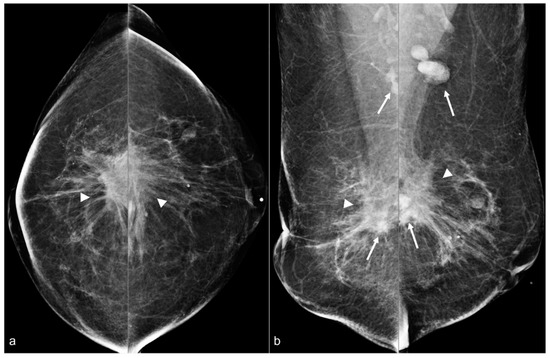

Figure 17. A 50-year-old woman with a history of subglandular silicone implants, status post BES. Screening mammograms with bilateral CC (a) and MLO views (b) demonstrate a mass in the left breast upper outer quadrant (arrowhead). BES changes are more prominent in the right breast with focal asymmetries in the prepectoral region (arrows) with dystrophic calcifications. Subsequent ultrasound examination of the left breast in the transverse plane (c) with ultrasound-guided biopsy revealed triple-negative invasive ductal carcinoma. T1-weighted post-contrast MRI (d) revealed a left breast enhancing mass (arrowhead) with a biopsy clip. There was also right greater than left prepectoral fluid (arrows) on the axial T2-weighted images (e).